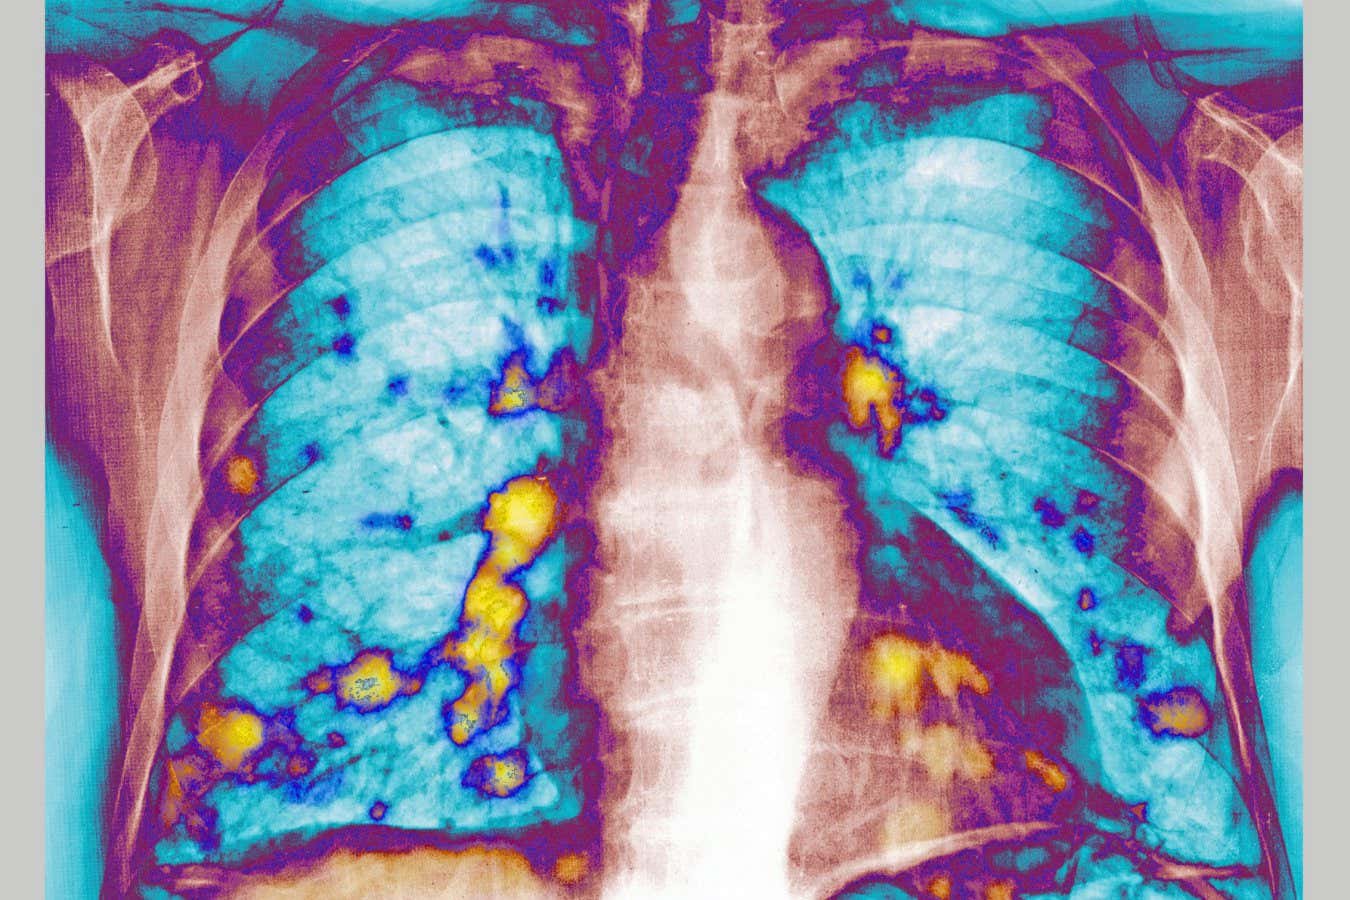

The lungs are one of the most common places for cancers to spread to from elsewhere in the body

The lungs are one of the most common sites for cancer to spread to, which has made the role of respiratory infections like flu, covid-19 and cold-causing viruses an area of considerable interest to scientists.